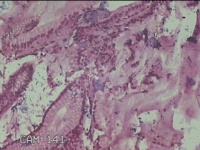

胃窦粘膜

性别

男

年龄

40岁

临床诊断

消化性溃疡

一般病史

胃窦近小弯侧近胃角,后壁可见直径0.3x0.4cm广基息肉样隆起,表面粗糙。

标本名称

大体所见

灰白粉红色组织小米大2团。

良性病变。